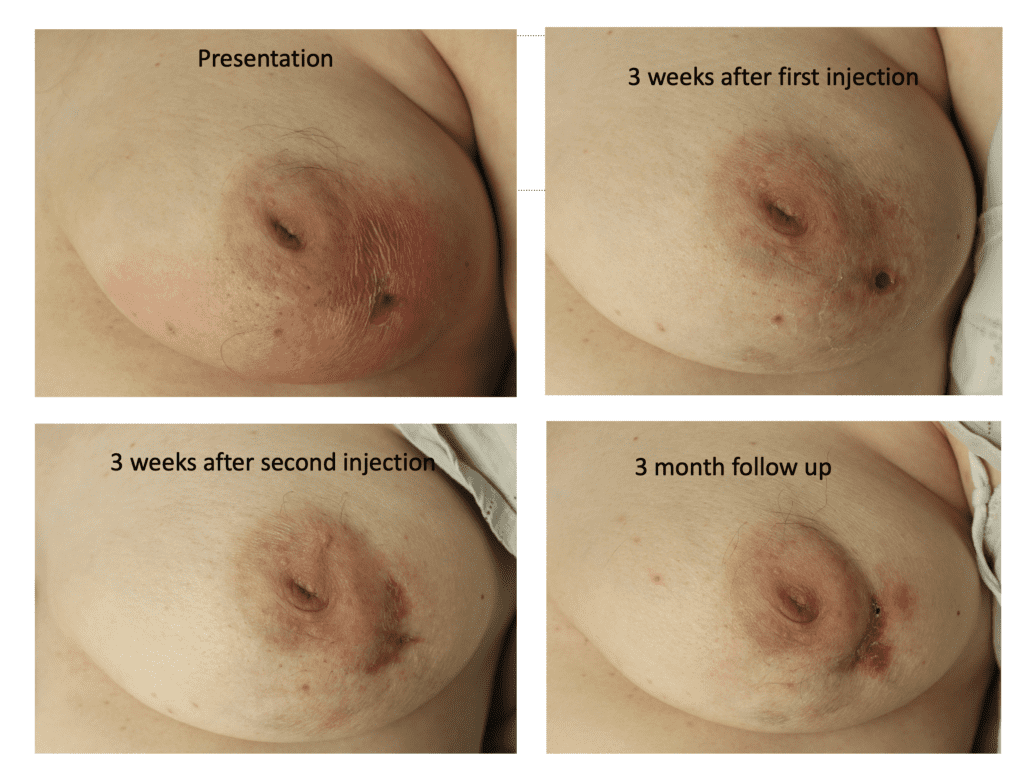

Idiopathic Granulomatous Mastitis (IGM or GM)

Idiopathic granulomatous mastitis (IGM) is an inflammatory disorder affecting the breast of young women in their childbearing years, and can overlap with lactation and pregnancy. It can result in development of painful inflammatory masses, fluid collections, and fistula formation. While breastfeeding from the affected breast in the setting of IGM is safe, many mothers report significant pain and difficulty with latch or milk production.

The definitive treatment for IGM is immunosuppression with the oral medications methotrexate (not safe with lactation or pregnancy) or azathioprine (safe with pregnancy and lactation). This case report describes continued breastfeeding and resolution of IGM with azathioprine therapy.

I have had similarly impressive results in my IGM patient population. I first prescribed LDN in the summer of 2024, and the patient resolved completely by the fall. Many others have resolved within just a month or two. All have experienced improvement within a month. Only one of my patients has remained symptomatic, but her disease is far better and far less painful than before (consistent with the Crohn’s Disease literature). Some of these patients are pictured below – keep scrolling :).

Another option for treating a flare of IGM is a steroid injection into the affected breast. This video that I presented at the American Society of Breast Surgeons in Boston spring 2023 illustrates this procedure:

While some cases of IGM may resolve from a simple mass, many go on to form fluid collections (above and below) that may drain on their own. These are mistakingly called “abscesses.” They are in fact just fluid collections of dead inflammatory cells. Patients need either local treatment with needle drainage of the fluid (NOT large incisions with packing tape, which make inflammation worse) and steroid injection, or oral steroids/anti-inflammatories/immune suppressants.